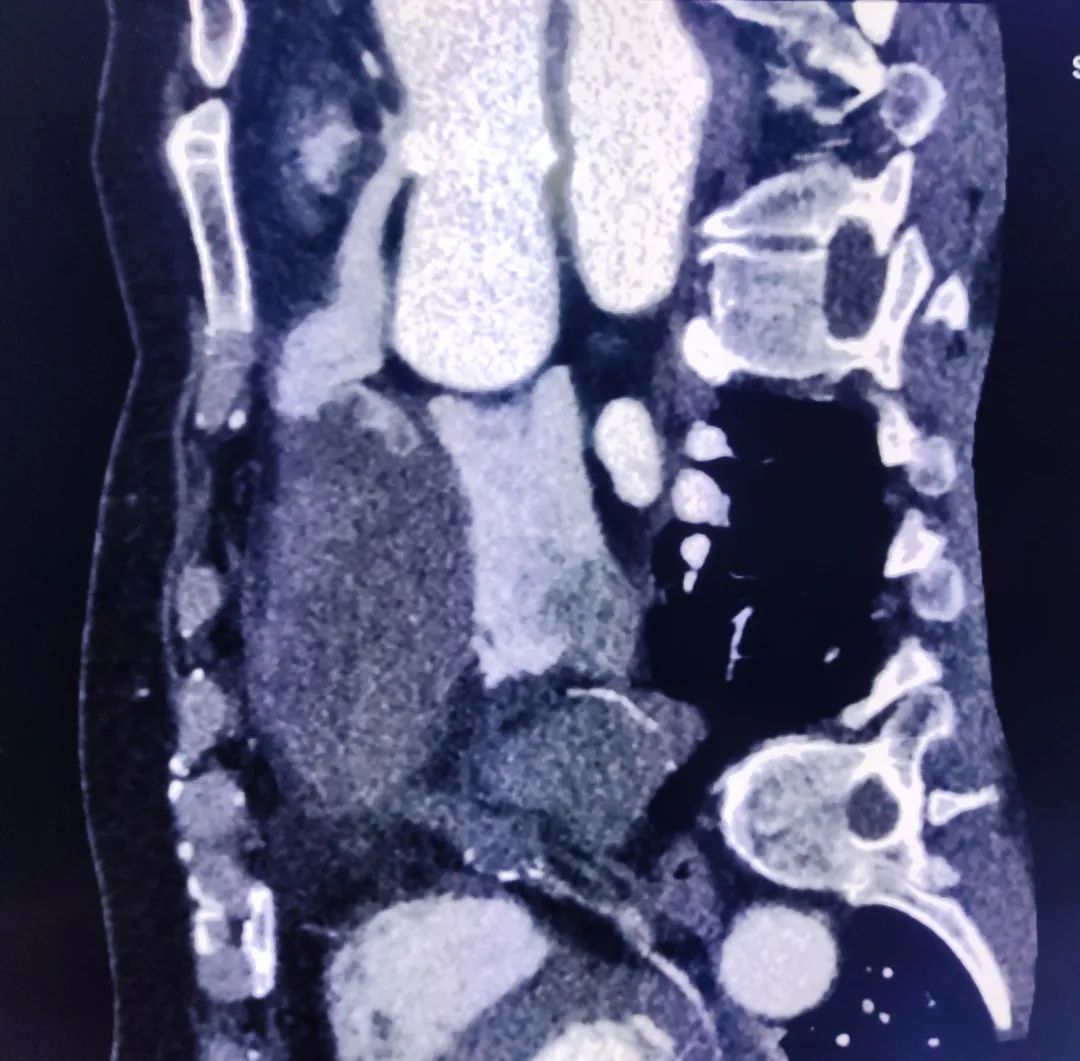

冠状动脉瘤的形成原因在于,各种因素影响下动脉中膜层弹力板断裂破坏,动脉内压力作用下管壁逐渐膨胀,形成瘤样扩张结构。

巨大动脉瘤原因排除冠脉粥样硬化。